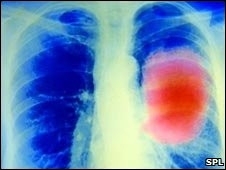

Os altos níveis de vitamina B6 e do aminoácido metionina cortam o risco pela metade, sugere o estudo, que acompanhou 400 mil pessoas por oito anos.

O estudo acompanhou quase 400 mil pessoas em 10 países europeus ao longo de oito anos.

Independentemente de fumarem ou não, as pessoas com níveis mais altos de vitamina B6 e metionina no sangue pareciam estar protegidas contra o câncer de pulmão.

Um número muito menor de pessoas neste grupo desenvolveu tumores no pulmão ao longo do estudo, em comparação com as pessoas com a concentração mais baixa destes nutrientes no sangue – 129 pessoas contra 408 respectivamente, de um total de 899 casos de câncer entre os pacientes acompanhados.